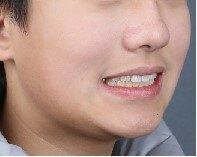

治疗前

11岁小男孩,主诉龅牙,牙齿不整齐。

检查:侧貌突,开唇露齿。上颌前突,下颌后缩,上前牙前突10mm左右,咬合深,咬至上颌粘膜,上下牙弓狭窄,牙列拥挤不齐。